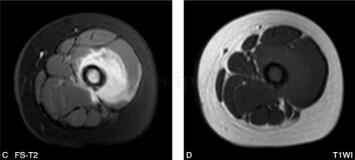

女,5岁,左下肢疼痛月余,近日加重,左下肢活动受限。病来无发热盗汗,无结核接触史。查体:左大腿肿胀,皮温略高,有压痛(图1、图2)。

图2 MR:左股骨中上段髓腔内见长T1、长T2信号改变,局部肿胀增粗,左股骨局部外侧缘见层状骨膜反应,周围肌肉组织呈长T1、长T2信号改变